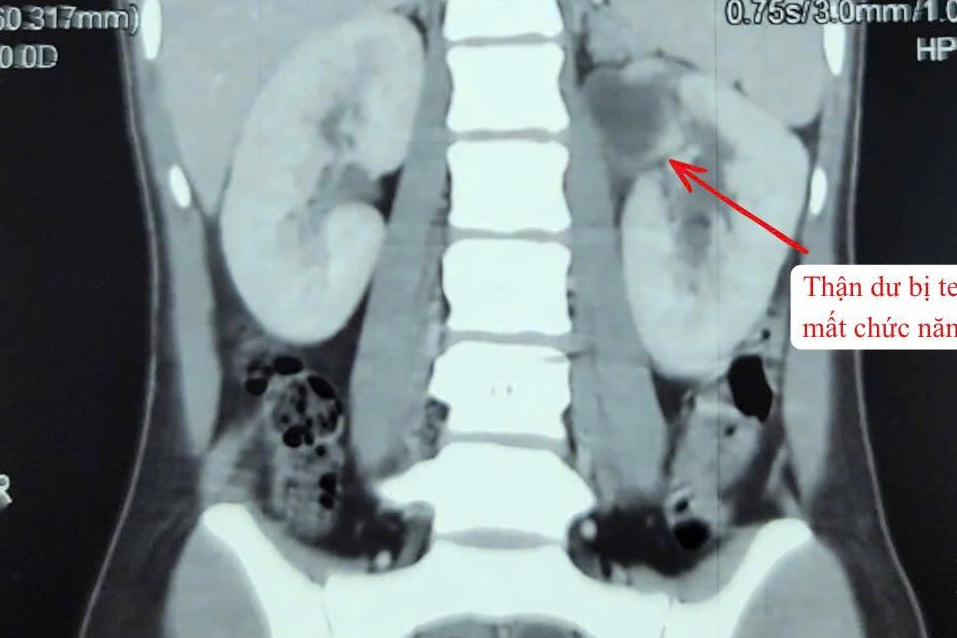

Căn bệnh khiến một bên thận của bé trai 4 tuổi teo nhỏ

Kết quả siêu âm cho thấy bệnh nhi chỉ có một quả thận, phần còn lại dù có nhưng đã bị teo bẩm sinh.